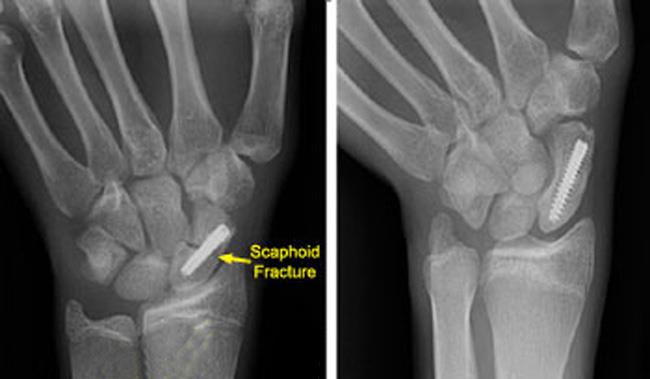

치료는 위의 Herbert 분류에 따라 각각 다를 수 있습니다.

Herbert A의 경우 경과관찰(캐스트, 롱암썸스피카) 을 하여도 유합되는 경우가 많지만 근위 첨부의 골절의 경우 전위 유무와 상관없이 불안전성으로 간주하고 후방도달법을 이용해 수술적 치료를 하여야 합니다.

Herbert B의 경우 전위가 없거나, 최소한의 전위가 있는 경우 경피적 나사고정을 시행해 볼 수 있습니다. 하지만 전위가 있거나 불안정한 경우, 정확한 정복술과 함께 관혈적나사내고정술이 시행되어야 합니다. 내고정 기기로는 K강선이나, Acutrak 나사, Herbert 나사, AO compression screw 등을 사용할 수 있습니다. 관혈적 정복술로는 Waist나 distal 1/3 골절의 경우 Volar approach를, Proximal pole 골절의 경우는 Dorsal approach를 시행할 수 있습니다. (혈관은 손등쪽에 위치하므로 주의하여야 하며 골이식이 필요한 경우에는 Volar approach 를 이용할 수 있습니다.)